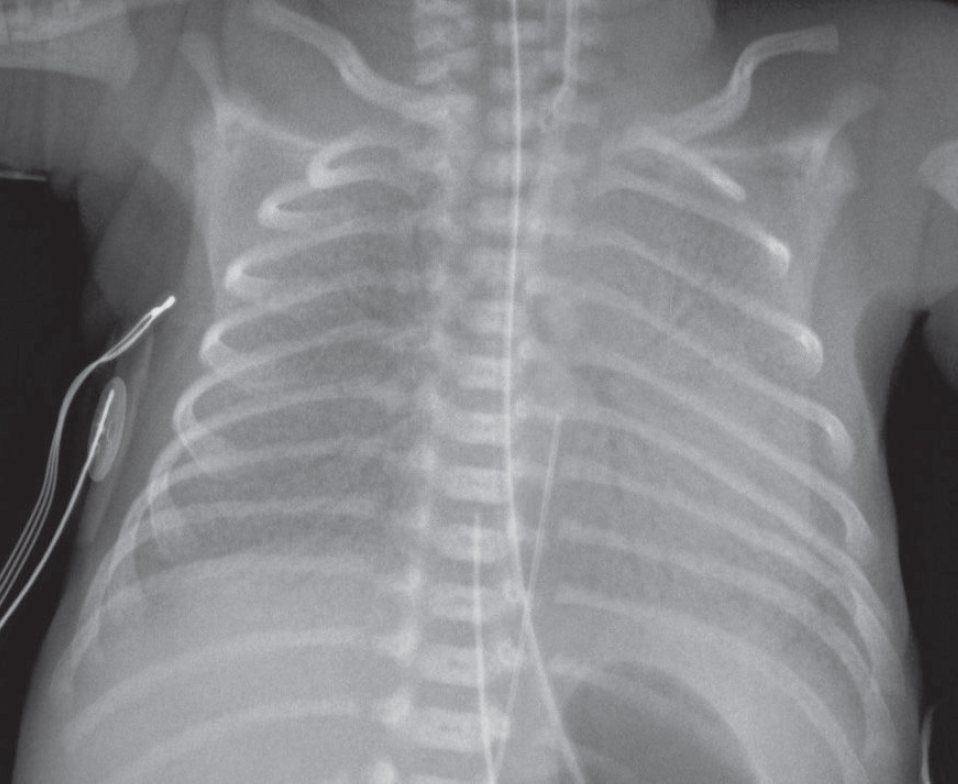

A Premature Newborn with Retractions, Grunting, and Poor Air Movement

1,260 g girl born at 30 weeks’ gestation presenting with retractions, grunting, and poor air movement and requiring oxygen; has received one dose of surfactant, with some clinical improvement.

What do you see on the Chest X-Ray ?